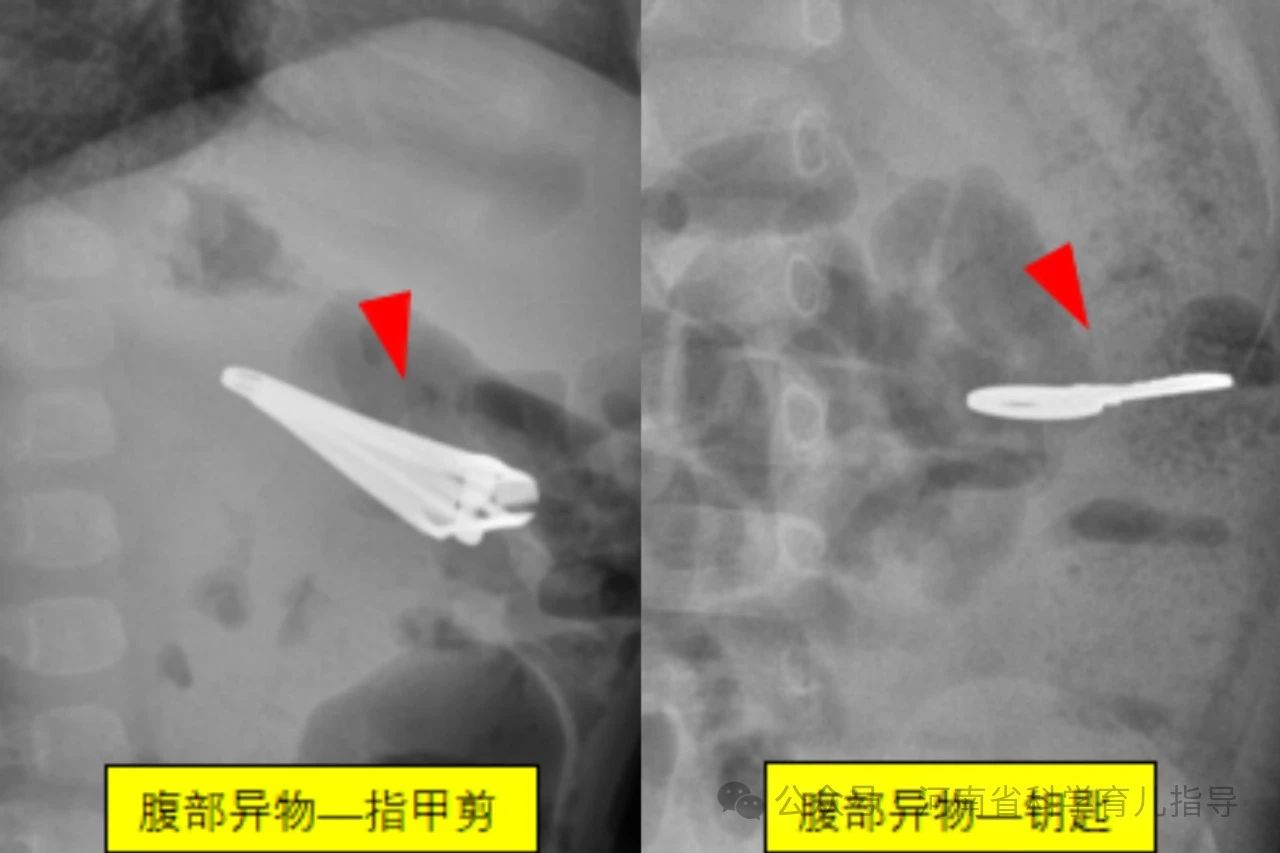

消化道异物儿童消化道异物是指儿童误吞了不能被消化且未及时排出而滞留在消化道的各种物体,文献中已报道的有硬币、果核、碎骨、电池、磁性异物、玩具、指甲、乳牙、笔头、塑料笔帽、电动牙刷头、大头针、戒指、图钉、螺丝钉、别针、纽扣、毛发等等。根据其形状主要包括以下几种,圆钝型异物如硬币,钢珠,螺丝帽,电池,棋子等圆形或者边缘比较平钝、光滑的物体,扁平状或球型。尖锐型异物如针状,钉状或者钩状物体,还有不规则型异物如女性的金属饰品发卡,生活用品如温度计中的水银等。其中形状不规则或者尖锐异物、纽扣电池、多枚磁性异物或单枚磁性异物合并金属异物发生并发症的风险较高,危险性较大。

经搜集我们郑州大学第三附属医院医学影像科最近7年间的图像存储系统的X线报告,查找可疑小儿消化道异物的病例541例,即家长发现家中某些东西不见了,但未直接看见或不确定孩子是否吞咽异物。通过X线拍片检查确认存在消化道异物病例共338例,阳性病例约62.5%。338例消化道异物中硬币183例,磁力珠15例,电池20例,水银22例,磁铁3例,钢针7例,钢珠10例,钉类14例,围棋子7例,其他个别如发卡,手链,钥匙,戒指,果核,易拉罐环,子弹头,纽扣,拉链等少数。发生消化道异物的小儿年龄最小的3个月,最大的6岁。23例在1岁以内,且多数在6个月到1岁之间;1岁74例,2岁94例,3岁77例,4岁43例,5岁24例,6岁3例。由此可以看出小儿发生消化道异物的年龄大多数在1~5岁之间,当然1岁以下甚至3个月的小婴儿也可以发生,这需要家长朋友们特别注意。

下面来看一组尖锐型消化道异物,下图。